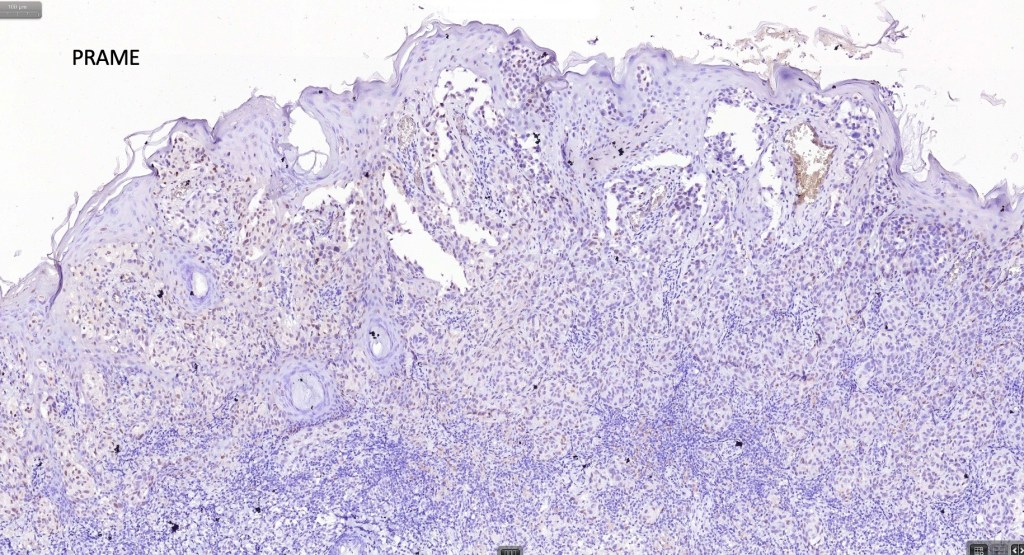

•S100, MART1 & SOX10 +ve, HMB45 +ve (superficially & lost progressively with depth), p16 +ve, p21 +ve

. BRAF -ve